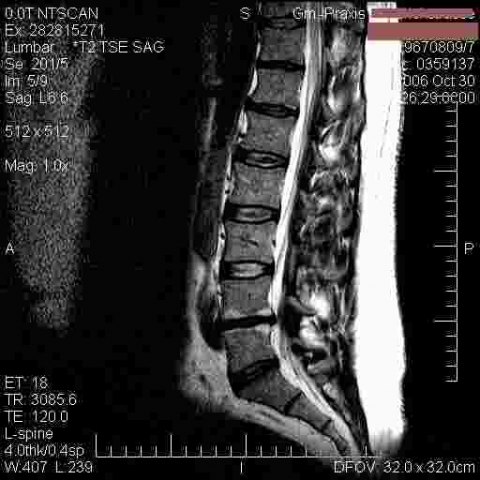

Ein Bandscheibenvorfall kann am besten in der Kernspintomographie (MRT) festgestellt werden. Gelegentlich ist jedoch aufgrund der Symptomatik, z.B. Sensibilitätsstörung oder Muskelschwäche, bereits ein Bandscheibenvorfall zu vermuten. Auch diese Vermutung muss aber mit der MRT überprüft werden. Allein vom Röntgenbild oder der Schilderung ihrer Beschwerden kann kein Bandscheibenvorfall diagnostiziert werden.